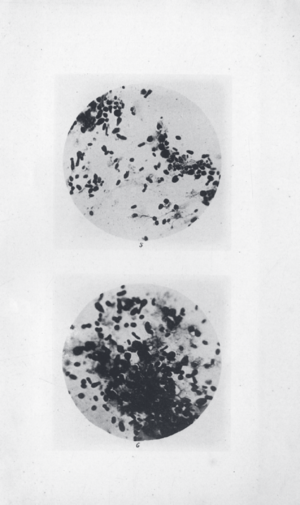

| A scanning electron micrograph depicting a mass of Yersinia pestis bacteria in the foregut of an infected flea | |

Yersinia pestis (formerly Pasteurella pestis) is a gram-negative, non-motile, rod-shaped, coccobacillus bacterium, without spores. It is a facultative anaerobic organism that can infect humans via the Oriental rat flea (Xenopsylla cheopis).[1] It causes the disease plague, which takes three main forms: pneumonic, septicemic, and bubonic.[1][2]